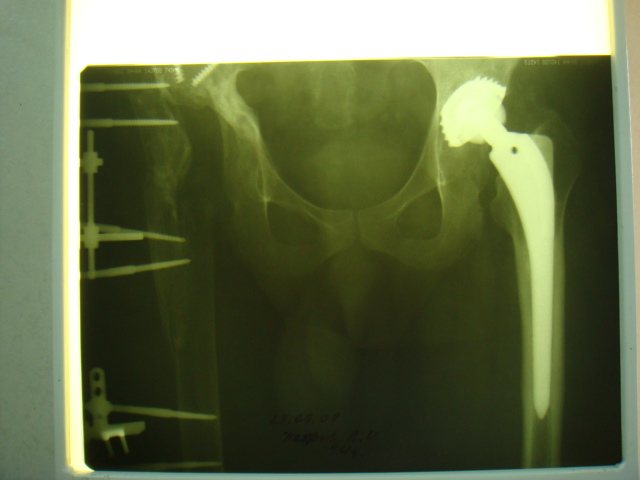

2003 г. нестабильность тазового компонента (рис. 2) - протез удален.

2005 г. при падении с высоты - перелом бедра в верхней трети, наложение АВФ . 3 года пациент ходил с аппаратом(рис. 3).